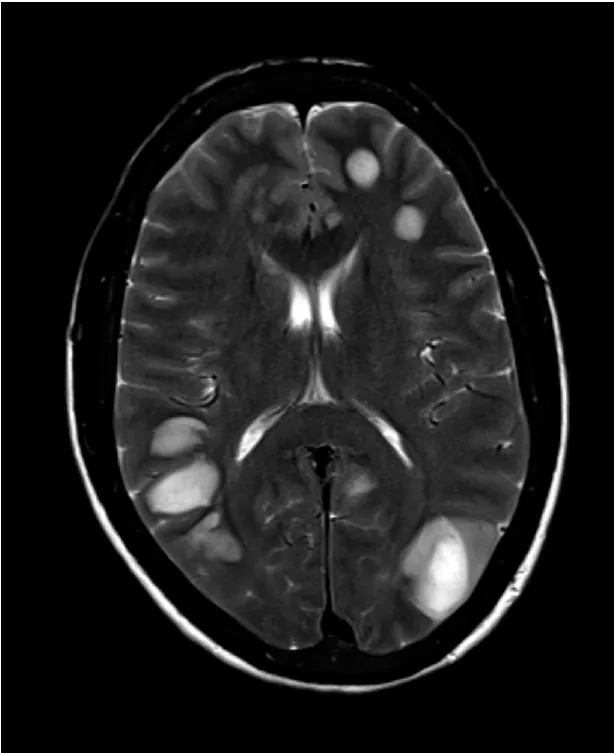

IRA + Icterícia: Um Caso que Exige Investigação Detalhada